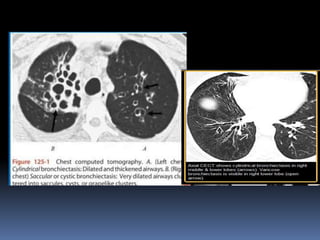

BRONQUIECTASIA  dilatación bronquiallocalizada o difusa, generalmente como resultado de una infección crónica, obstrucción de las vías proximal, o anomalía congénita bronquial .  Rx y TAC .-criterios en cortes finos CT exploraciones incluyen dilatación bronquial con respecto a la pulmonar (signo de anillo de sello), identificación de los bronquios dentro de 1 cm de la superficie pleural. Bronquiectasia pueden clasificarse como cilíndricas, varicosas o quístico, dependiendo en la apariencia de la afectada bronquios. A menudo es acompañado por el engrosamiento de la pared bronquial, mucoso impactación, y anormalidades de las vías aéreas de pequeño